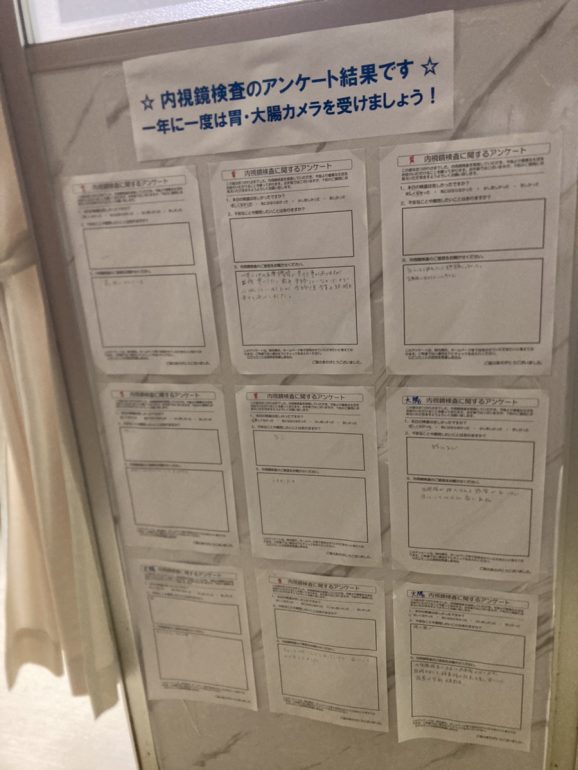

2021年9月から当院で内視鏡検査を受けられた方へのアンケートを開始しました。

80%の患者さまが、「苦しくなかった」「気にならなかった」とお答えいただけました!

苦しくなかった 33名 68%

気にならなかった 6名 12%

少し苦しかった 9名 18%

苦しかった 0名 0%

麻酔を使わずに検査を受けられた方々に「少し苦しかった」とのご回答が多かったようです。今後も苦痛の少ない内視鏡検査を目指して精進いたします。

【アンケートに実際に書き込んで頂いたご意見ご感想(原文のまま、一部抜粋)】

・眠っている間に検査が終わって、全く覚えていないまま苦しい思いもせず出来たので、大変良かったです。先生・スタッフの方もとても優しく、大満足です。

・麻酔がきいて、いつの間にか終わってて、ぐっすりねてしまいました。痛みもなく検査してもらって良かったです。年なので、一年に1回は受けていいのかなと思いました。明日、会社の人達にも検査する事をすすめたいと思いました。

・内視鏡が挿入される感覚がないほど思っていた以上に楽であった。

・気づいたら終わっていて、全然苦痛じゃなかった。定期的に受けてもいいと思えた。

・どうなるか心配していましたが、全然心配する事なかったです。毎年1回検査します。

・ハナが少し痛かったくらいでとくに問題は感じませんでした。

・眠ってる間に終わっていて、ビックリしました。楽でしたので、又受けたいと思いました。

・鎮静剤の使用で、いつの間にか終わっていたので、楽でした。先生の説明もしっかりしてもらって安心しました。

・最高に良かったです。いつもありがとうございます!お世話になってます。また来年来ます。

・苦しくありませんでした。今までの中で一番痛くなくて良かったです。

ご協力ありがとうございました。今後も創意工夫し痛みの少ない内視鏡検査をがんばります!

当院では内視鏡検査の品質向上のため、患者様にアンケートのご協力をお願いしております。

貴重なご意見ありがとうございます。

今後も安心・安全な医療を皆様に提供できるようスタッフ一同努めて参ります。